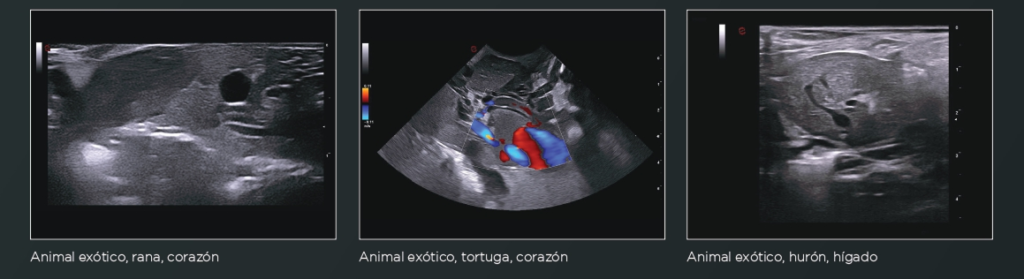

Imágenes Clínicas